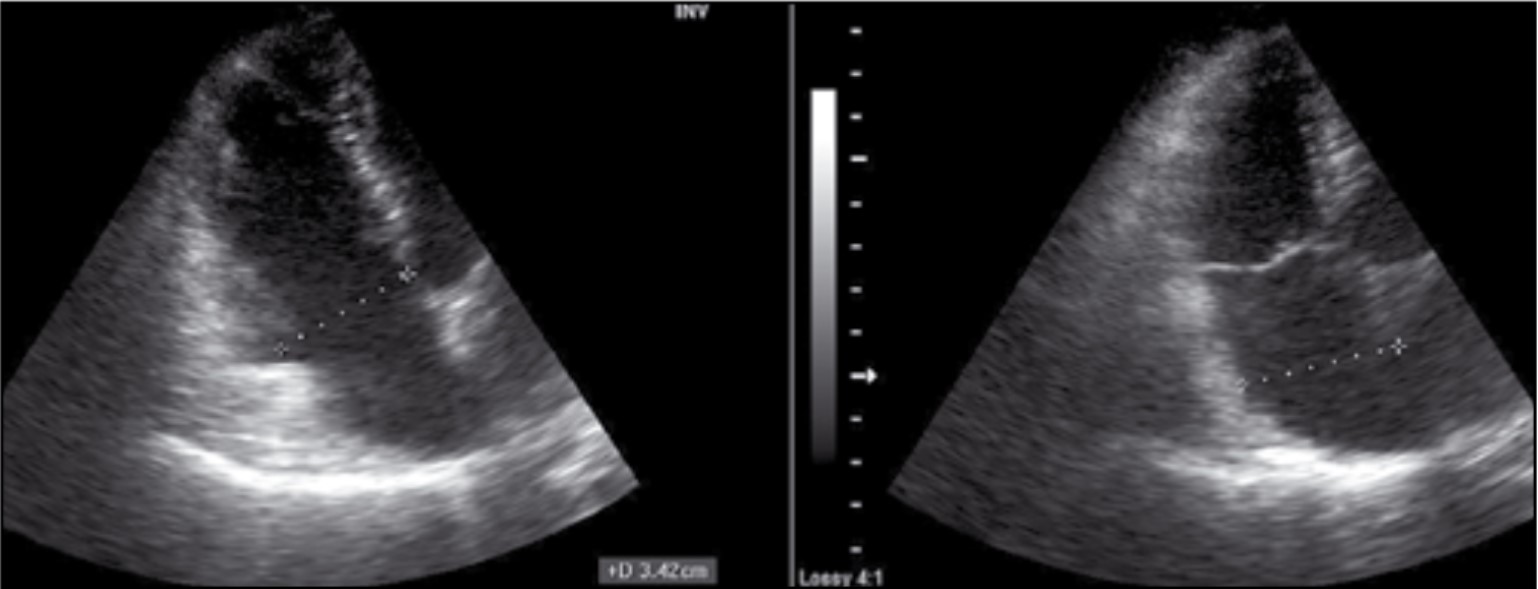

Праві відділи серця не дилатовані – поперечний розмір правого шлуночка (ПШ) у діастолу – 3,4 см; поперечний розмір правого передсердя (ПП) у систолу – 3,75 см; функції тристулкового клапана (ТК) без порушення (рис. 5).

Рис. 5. Розміри правих відділів серця в позиції А4С